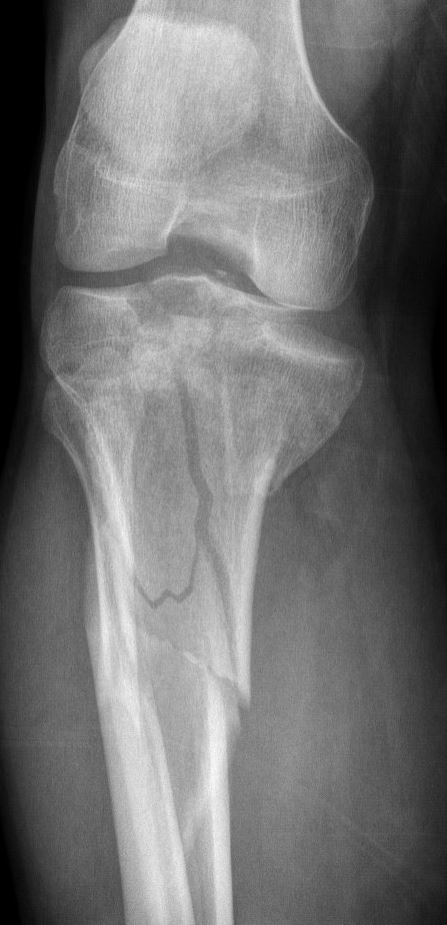

De breuk

Een breuk van het tibia plateau ontstaat door fors inwerkend geweld, vaak door een verkeersongeval of val van hoogte, waarbij de knie meestal geforceerd naar binnen of naar buiten beweegt. Daarmee komt er zoveel druk op het plateau dat deze het begeeft en aan de binnen of buitenkant (of beide) breekt. Hierbij zakt dat gedeelte van het plateau vaak in. Naast het bot raakt dan ook altijd het kraakbeen beschadigd, maar vaak ook de meniscus of zelfs de kruisbanden.

Afhankelijk van de stand van de breuk en het gewrichtsoppervlak, kan de breuk in gips worden behandeld of zal er een operatie noodzakelijk zijn.

Meestal zal er echter een operatie nodig zijn om het hoogteverlies in het plateau te corrigeren en het gewrichtsoppervlak zo goed mogelijk te herstellen en vast te zetten. Als de zwelling door de breuk direct te groot is, kan het zijn dat deze operatie wordt uitgesteld totdat de zwelling is afgenomen.